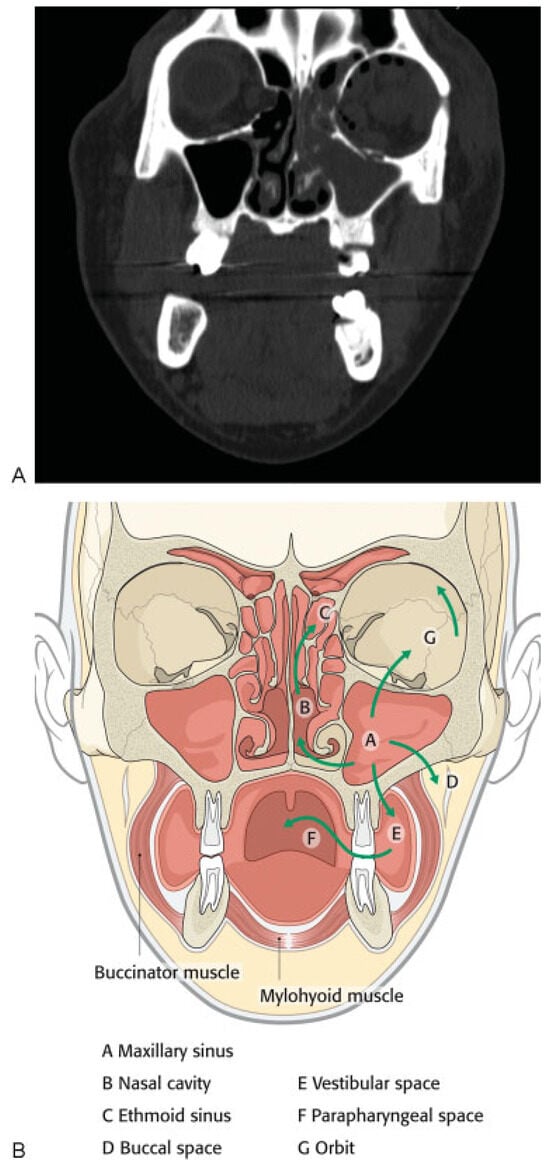

A 43-year-old woman presented to our clinic with a complaint of left sided facial pain and periorbital swelling secondary to her involvement in a motor vehicle collision the previous night. She reported no other injuries. Her medical history was significant for diabetes mellitus type II which was poorly controlled and hypertension for which she was taking metformin, glyburide, and lisinopril. The patient also had amblyopia in her left eye since childhood resulting in poor vision and diplopia. Her past surgical history was significant for cataract surgery of the left eye in 2009. A maxillofacial CT scan revealed a minimally displaced left orbital floor and medial orbital wall fractures (►Figure 1A). In the clinic, the patient was afebrile with stable vital signs. Her finger stick blood glucose (FSBG) was measured as 363. On physical examination, her left periorbita was edematous and she had tenderness to palpation of the left periorbital, temporal, and zygomatic regions, which were all consistent and normal with expected posttraumatic signs. Her vision in the right eye and left eye was 20/25 and 20/400, respectively, and the patient denied any acute visual acuity changes. Of note, 20/200 is considered legally blind in the United States. Bilateral extraocular movements were intact with no evidence of entrapment. Cranial nerve examination revealed grossly intact cranial nerves 3 to 12 with the exception being the left eye having vision changes of 20/400 and cranial nerve V2 paresthesia. Glasgow Coma Scale score was 15. The patient was prescribed pain medication, and asked to return to clinic in 4 days for reevaluation once the swelling subsided for surgical workup. The patient was sent to ophthalmology clinic that day and was evaluated. She was not prescribed antibiotics.

In this case, we believe that the infection originated in the maxillary sinus and extended into the orbital cavity through the fractured orbital floor, resulting in preseptal and postseptal orbital cellulitis progressing to abscess. The infection then likely spread to the face via the ophthalmic and angular vein, reaching the left buccal space. The lack of host response secondary to uncontrolled diabetes mellitus may have contributed to further dissemination of the infection to two other ipsilateral spaces: (1) from the maxillary sinus to the nasal cavity through the medial maxillary sinus wall and (2) from the buccal to the parapharyngeal space through the pterygomandibular raphe, a ligamentous band of the buccopharyngeal fascia, located between the superior pharyngeal constrictor and the middle portion of the buccinator muscles (►Figure 1B).

Figure 1. (A) Coronal computed tomographic scan showing minimally displaced left orbital floor and medial wall fractures, total opacification of left maxillary and ethmoid sinuses, and partial opacification of frontal sinus. Healed previous injury to right medial orbital wall was noted. (B) Route of infection extending from maxillary sinus to orbit, nasal cavity, ethmoid sinus, buccal space, and parapharyngeal space.